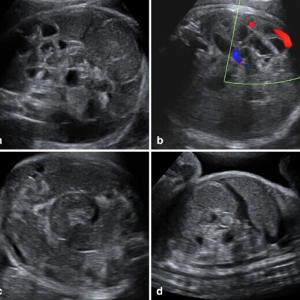

胎儿肠扭转一例

近期来自德国萨莱大学妇产科的Takacs ZF医师在Arch Gynecol Obstet杂志上发表了一例胎儿肠扭转的案例。一名35岁初产妇,孕龄到达30周时出现了宫缩征象,但没有显示胎儿窘迫。超声显示胎儿发育,多普勒指数,羊水均正 ...